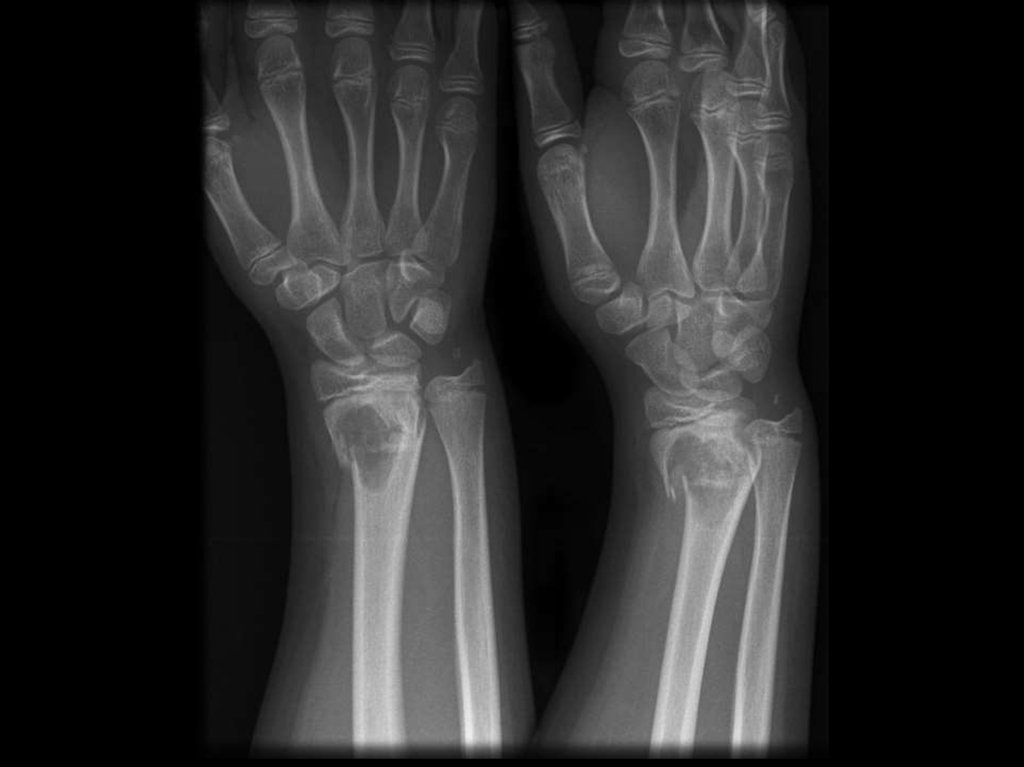

15. Локализация переломов

Позвонки

Шейка бедра

Предплечье

Примеры диагноза:

Первичный

постменопаузальный

ОП

с

болевым синдромом. ФН 1.

Тяжёлый стероидный ОП с компрессионным

переломом в грудном отделе позвоночника

(Th 12 – L1), перелом предплечья (в 1998 г).